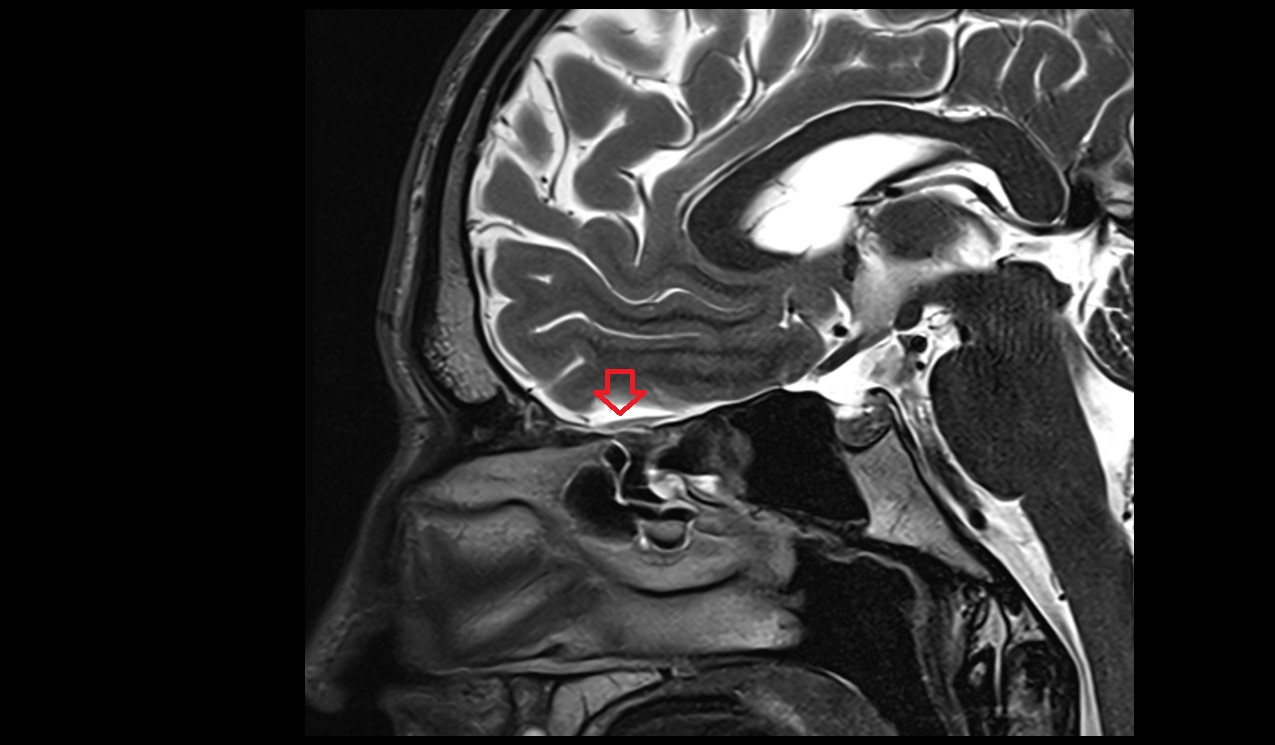

- Pituitary stalk